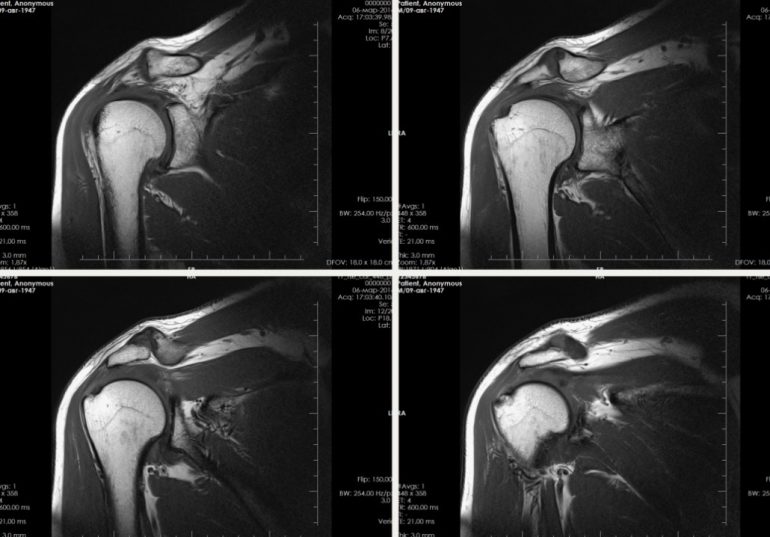

Магнитно-резонансная томография (МРТ) плечевого сустава является одним из самых точных методов диагностики заболеваний и травм этой области. Она позволяет выявить даже незначительные изменения в мягких тканях, хрящах и костях, что делает её незаменимой при сложных клинических случаях. Проведение мрт плечевого сустава в Москве рекомендуется при ряде симптомов, таких как боль, ограничение подвижности или подозрение на воспалительные процессы. Важно понимать, в каких ситуациях этот метод диагностики необходим, а также как правильно подготовиться к процедуре для получения максимально точных результатов.

МРТ плечевого сустава является важным инструментом диагностики при травмах и заболеваниях этой области. Оно позволяет получить детальную информацию о состоянии мягких тканей и суставов, что делает его незаменимым при сложных случаях. Подготовка к исследованию минимальна и не требует значительных усилий со стороны пациента. Если вы столкнулись с болями или ограничением подвижности в плече, проконсультируйтесь с врачом о необходимости проведения данного обследования.